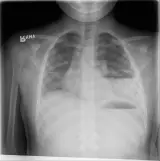

Over 2,100 interactive radiology cases, curated by radiologists for your level of training. Scroll, window, and view cases full screen โ€” just like on PACS. Click linked findings in each writeup to jump straight to them on the image. Cases include sample reports, a focused discussion section, original illustrations, and videos.

PACS์—์„œ ๊ธฐ๋Œ€ํ•  ์ˆ˜ ์žˆ๋Š” ๋ชจ๋“  ๋„๊ตฌ๋ฅผ ๊ฐ–์ถ˜ ์™„์ „ํ•œ ์ธํ„ฐ๋ž™ํ‹ฐ๋ธŒ ์ฆ๋ก€ — ์Šคํฌ๋กค, ์œˆ๋„์šฐ ์กฐ์ ˆ, ํ™•๋Œ€/์ถ•์†Œ, ํŒจ๋‹, ๊ณ„์ธก, ROI, ์ „์ฒด ํ™”๋ฉด ๋ชจ๋“œ๊นŒ์ง€ ์ง€์›ํ•ฉ๋‹ˆ๋‹ค.

์ฃผ์š” ์†Œ๊ฒฌ์„ ์ฆ๋ก€์— ์ง์ ‘ ํ‘œ์‹œํ•˜๋Š” ํ’๋ถ€ํ•œ ์ฃผ์„์ด ํฌํ•จ๋˜์–ด ์žˆ์Šต๋‹ˆ๋‹ค. ์ฆ๋ก€ ์„ค๋ช…์˜ ์—ฐ๊ฒฐ๋œ ์†Œ๊ฒฌ์„ ํด๋ฆญํ•˜๋ฉด ์Šค์บ” ๋‚ด ์ •ํ™•ํ•œ ์œ„์น˜๋กœ ๋ฐ”๋กœ ์ด๋™ํ•ฉ๋‹ˆ๋‹ค.

์–ด๋ ค์šด ์ฆ๋ก€๋ฅผ ์ •ํ™•ํžˆ ํŒ๋…ํ•˜๋Š” ๋น„๊ฒฐ์€ ๋Œ€๊ฐœ ์œ ์‚ฌํ•œ ์ฆ๋ก€๋ฅผ ์ด์ „์— ๋ณธ ์ ์ด ์žˆ๋Š”์ง€์— ๋‹ฌ๋ ค ์žˆ์Šต๋‹ˆ๋‹ค. ํฌ๊ด„์ ์ธ ์ง„๋‹จ ๋ชฉ๋ก์„ ์•„์šฐ๋ฅด๋Š” 1,900๊ฐœ ์ด์ƒ์˜ ์—„์„ ๋œ ์ฆ๋ก€๋กœ ์—ฐ์Šตํ•˜์„ธ์š”.